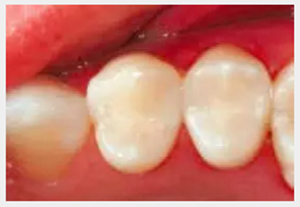

修復(fù)體使用一年后進(jìn)行漂白